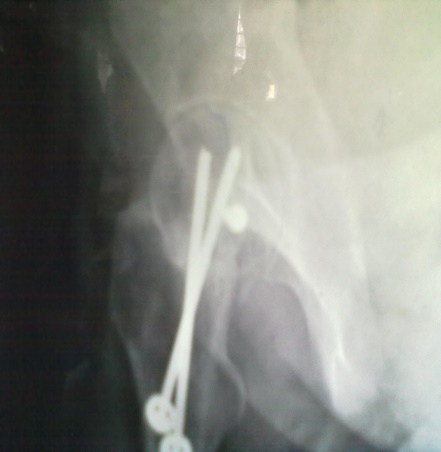

Spinal block was used in the procedure. Prone position on fracture table with radiolucent top was used. Fracture site was exposed through posterior approach and sclerosed margins of the fragments were freshened. Fracture was reduced with appropriate neck shaft angle and fixed with Moors pin/ knowels pin or 4 mm /7mm partially threaded cancellous screws. Any rotation or tilt was corrected. The fixation was augmented with quadratus femoris muscle pedicle bone graft harvested from intertochateric crest area with a bone pedicle of length 2 cm, width 1 cm and depth 1 cm. The graft was secured to the proximal femoral head fragment with 3.5mm cortical screw or 4mm cannulated cancellous screw. Soft tissue closure was done over drain.

First dressing change was done on third postoperative day and drain was removed at the same time. Sutures were removed on 14th day. Usually on 5th postoperative day quadriceps exercises was started. Non weight bearing was ensured for 4 months or till radiological union.

Patients were followed up at 2 weeks, 4 weeks, 6 weeks, 8weeksk, regularly at 6 week interval for next 6 month and then at three month interval up to two year. Radiographic analysis was performed at each follow up with special attention to extent of callus formation, alignment of fragments and hard ware integrity.